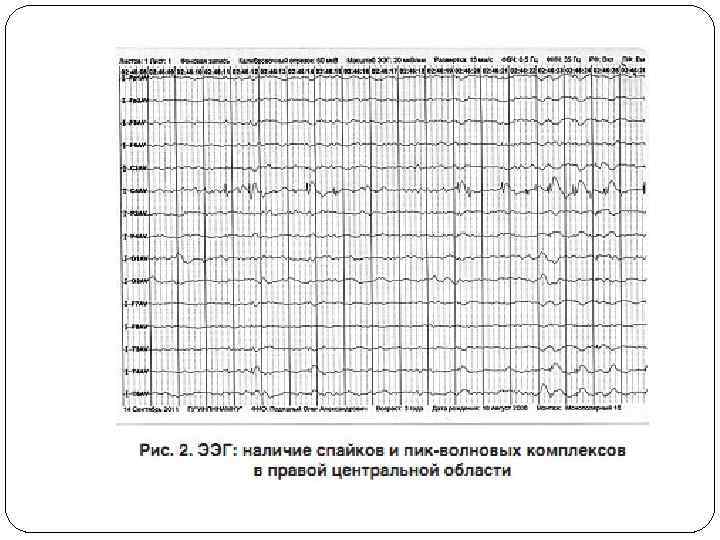

3. Плато. Период развития – от 2 до 10 лет. На этом этапе быстрая регрессия, наблюдаемая на втором этапе, замедляется. Возможно появление улучшений поведения, в частности, в виде снижения раздражительности. Дети становятся более активными и коммуникативными. Двигательные нарушения продолжают прогрессивно ухудшаться, плохо прибавляется вес. 4. Завершающая стадия. Отмечается в возрасте 10 лет и старше (может возникнуть в период от 5 до 25 лет). Характеризуется потерей подвижности. Способность ходить утрачивается (если она была приобретена). Появляются скованность в движениях, искривление позвоночника. Коммуникативные и когнитивные возможности, как правило, не уменьшаются. Стереотипии становятся реже. Нейрофизиологическое обследование в типичных случаях выявляет замедление фоновой биоэлектрической активности, наличие центральных спайков, а также редукцию «веретен сна» . Нейровизуализация показывает снижение объема вещества головного мозга (атрофии), как белого, так и серого, преимущественно в лобных долях.

Данные ЭЭГ Практически во всех случаях, даже у тех пациентов, которые не имеют клинических судорог, наблюдаются аномалии на электроэнцефалограмме, начиная примерно с двухлетнего возраста. Сочетание замедления фонового ритма в период бодрствования и повышенной пароксизмальной активности во время сна существенно облегчает диагностирование синдрома Ретта и может считаться его дополнительным диагностическим критерием. В большинстве случаев наблюдается характерная эволюция изменений на ЭЭГ. Примерно с шестилетнего возраста доминирует монотонный а-ритм, который в дальнейшем, после 20 лет, имеет тенденцию локализации в центро-париетальной области.